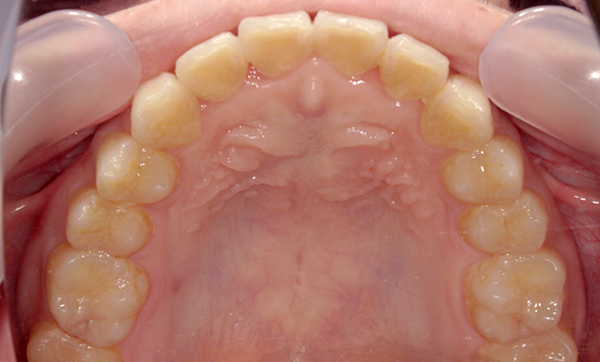

症例_009 「上下の前歯」症例

治療期間:7ヶ月金額:54万円+税20代女性捻転歯一部の反対咬合前歯のガタガタ